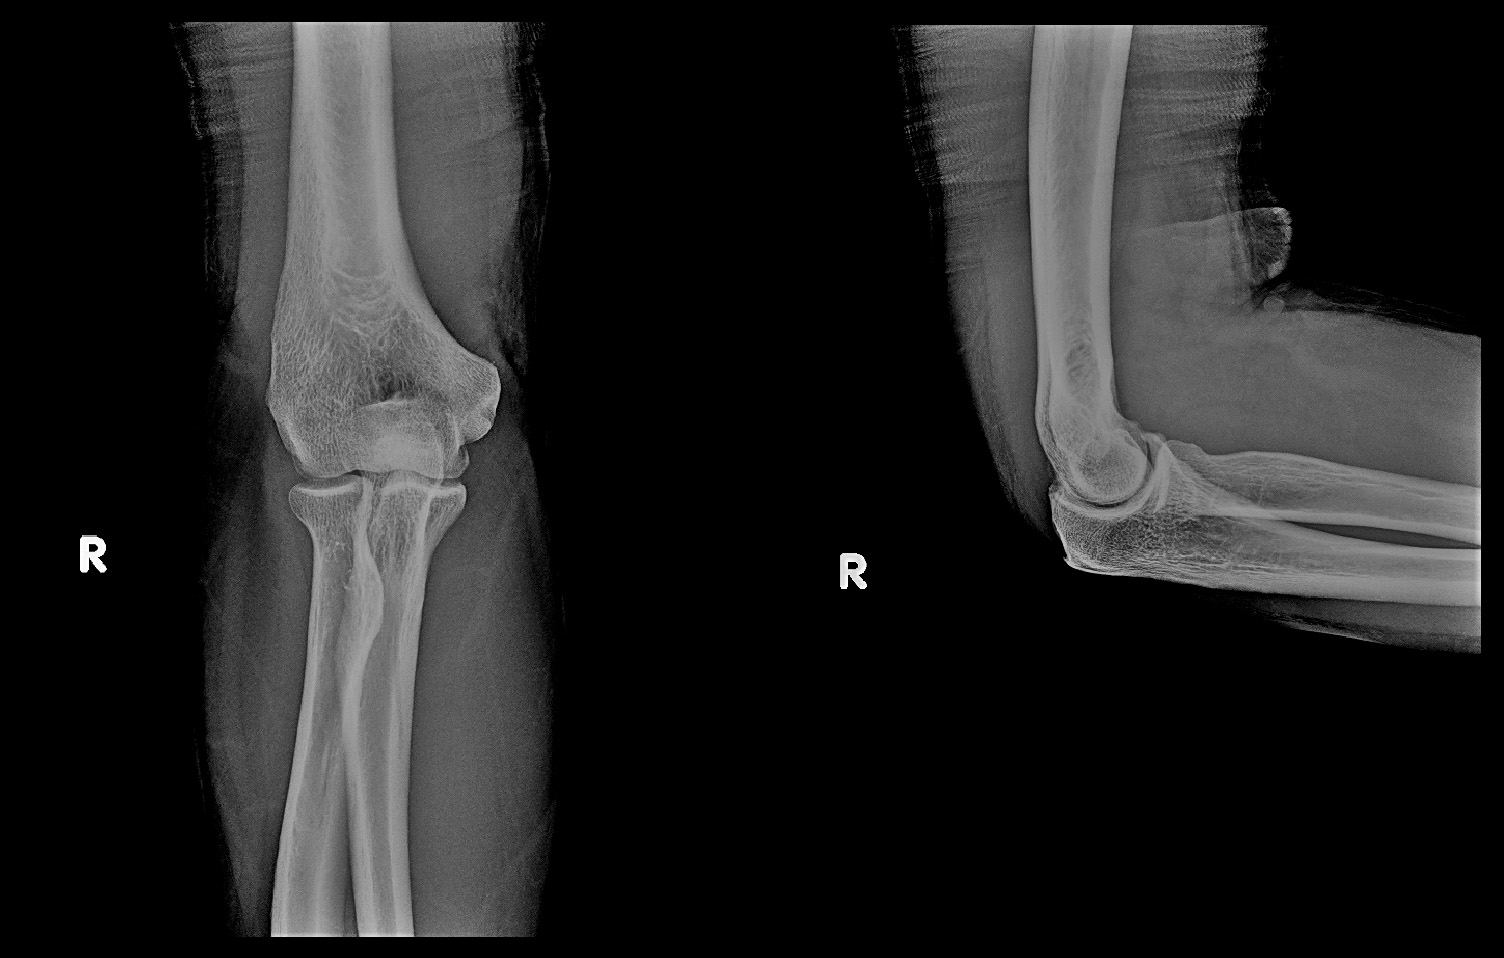

38才男 初診時Xp.jpg

初診時の左肘のレントゲン像です。左肘頭部とはオレンジ丸の領域ですが、異常を認めません。右肘に比して赤矢印の橈骨頭部と呼ばれる部分は左肘では四角く出っ張っていて、骨のラインは滑らかな曲線となっていません。この部分(橈骨頭部)に骨折があったと推察されます。橈骨頭部の骨折では手関節痛を訴えることはしばしばあります。